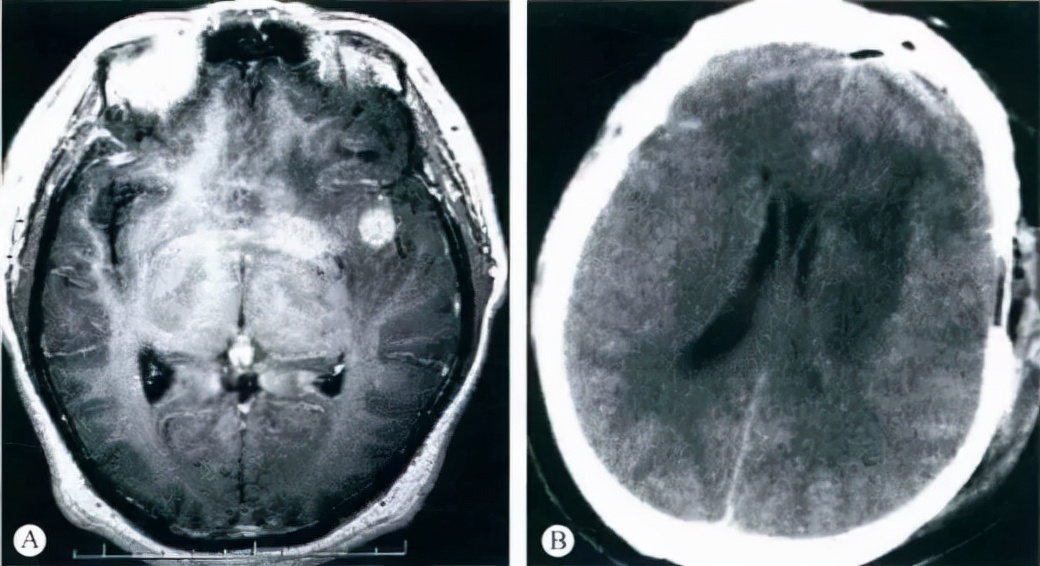

图:46岁男性,MRI显示右岛叶星形细胞瘤Ⅲ级(A)。右额颞开颅肿瘤切除,去骨片减压。手术后病人左侧偏瘫,神志不清。术后第二天CT显示基底核低密度,右侧脑室受压(B)。考虑为大脑中动脉痉挛受损所致